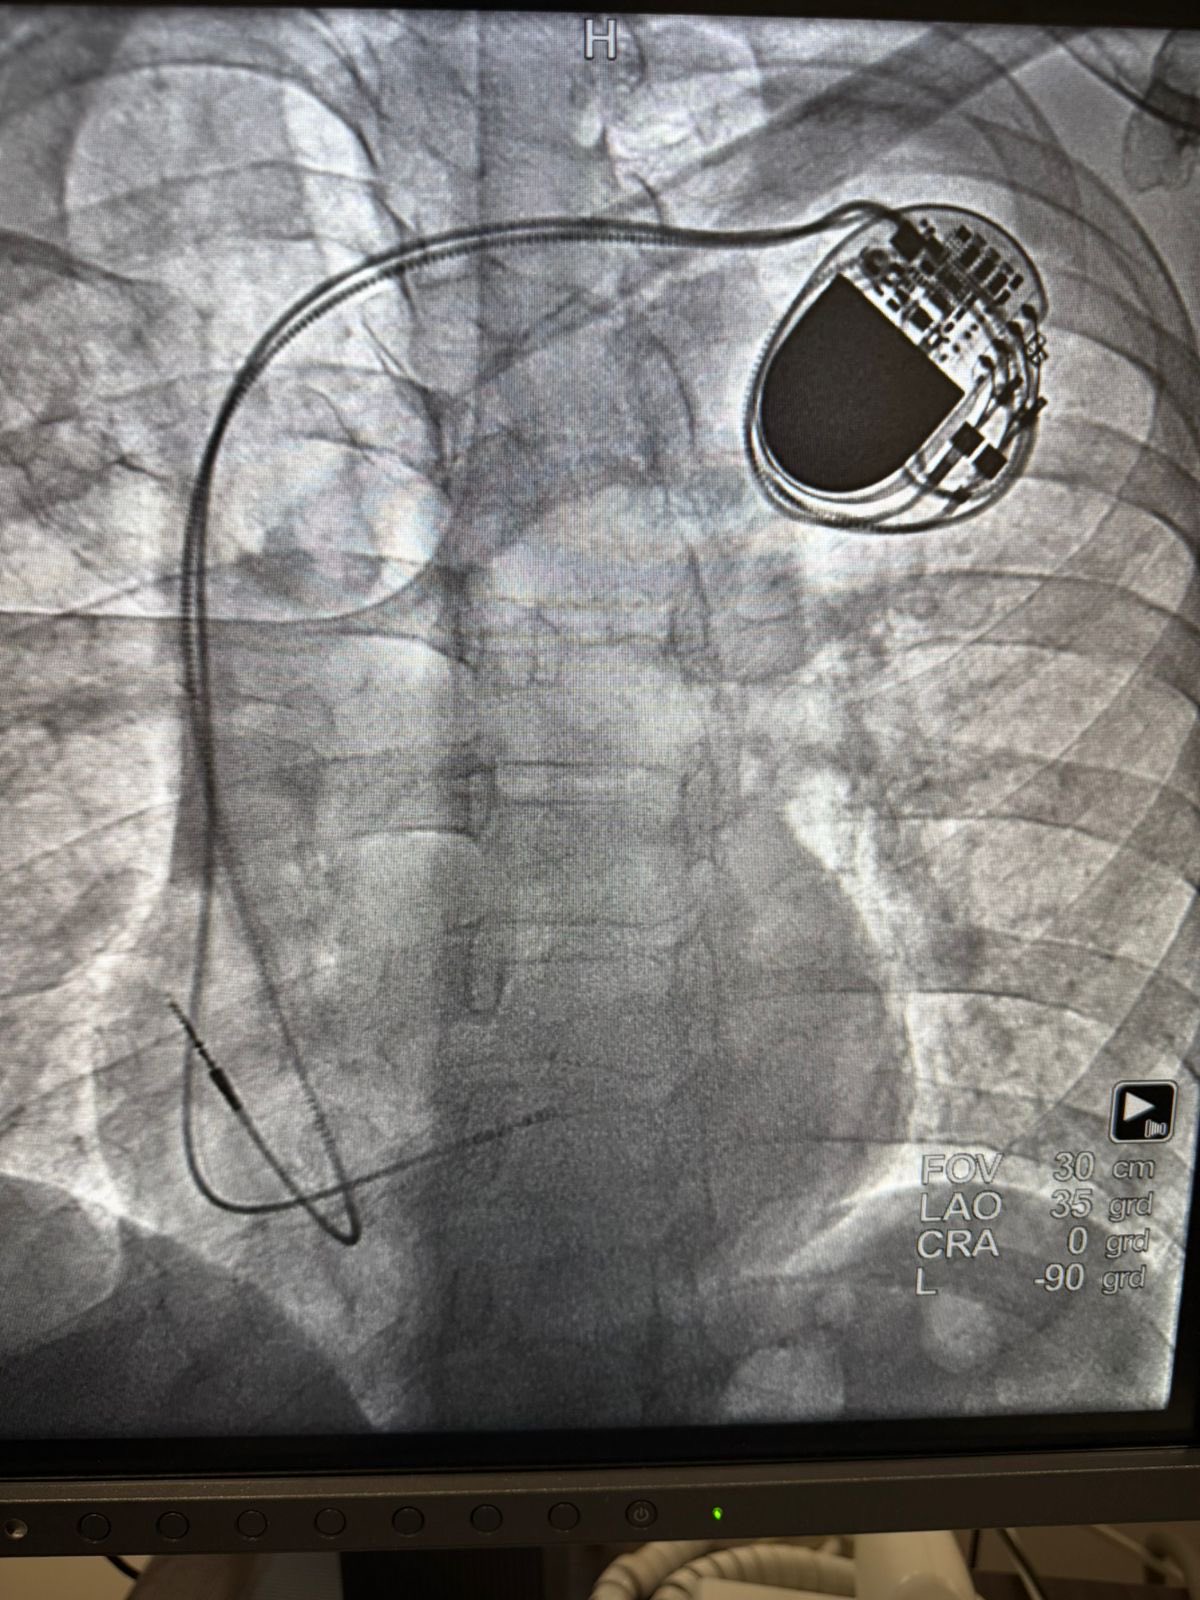

ISSSTE Veracruz @ISSSTE_Veracruz ·

🏥❤️ En Palenque, Chiapas, el ISSSTE realizó con éxito su primera jornada de hemodinamia. ✔️ 3 marcapasos ✔️ 2 cateterismos ✔️ 1 stent Se brindó atención especializada a 6 derechohabientes, acercando servicios de alta especialidad y reduciendo tiempos de espera.1